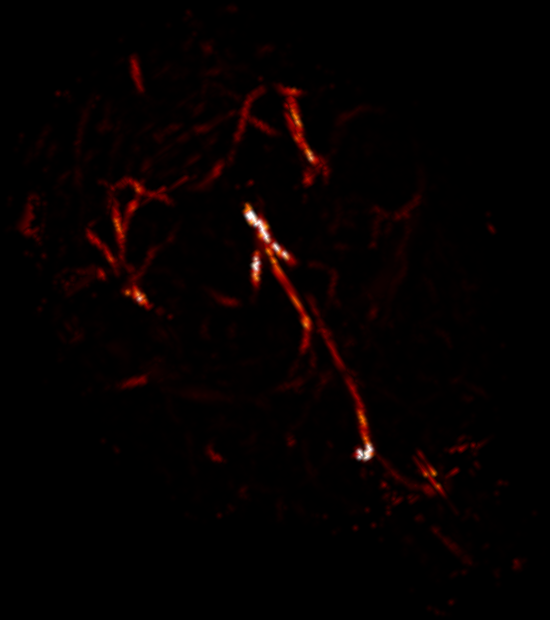

Using the same method as in 2D, namely TSP-sampling and projection onto the set of constraints, we reconstructed volumes from 3D -space. In order to estimate the quality of the reconstructions, we compared the angiograms computed from the 3D images using Frangi filtering [19]. The results are shown in Fig. 3 for acceleration factors (Fig. 3(b,e)) and (Fig. 3(c,f)) and compared to the angiogram computed from the whole data.

Using the strategy described in Part 3.1 the time to traverse -space would be 3.53 s (full acquisition), 3.15 s () and 0.88 s (). The main drawback of TSP-based sampling schemes is that the time reduction is not directly proportional to , in contrast to classical 2D downsampling and reading out along the third dimension. Nevertheless, if the number of measurements is fixed, the TSP-based approach leads to more accurate reconstruction results since the sampling scheme may fit any density [7].

Angiograms shown in Fig. 3 illustrate that one can reduce the travel time in the -space and still observe accurate microvascular structure. If , time reduction is minor (about 10% less), but the computed angiogram is almost the same as the one obtained with a complete -space. It is interesting to notice that with a higher acceleration factor (), the acquisition time is reduced by 75%, but the computed angiogram remains of good quality. The angiogram appears a bit noisier, especially in the pre-injection setting (Fig. 3(c)), but the post-injection image allows recovering Willis polygon and most of the major vessels of the mouse brain (Fig. 3(f)).